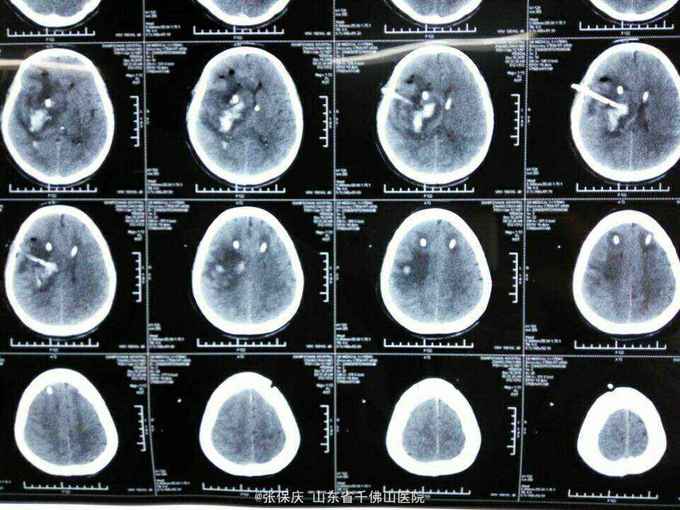

颅脑CT辅助检查 检查日期 项目 结果 2015-12-11 颅脑CT(人民医院) 右侧基底节区脑出血 2015-12-14 颅脑CT(人民医院) 右侧基底节区脑出血钻孔引流术后改变

诊断 : 1.右侧基底节区脑出血术后 2.高血压病(3级 极高危) 3.糖尿病 4.冠状动脉粥样硬化性心脏病 5.发热